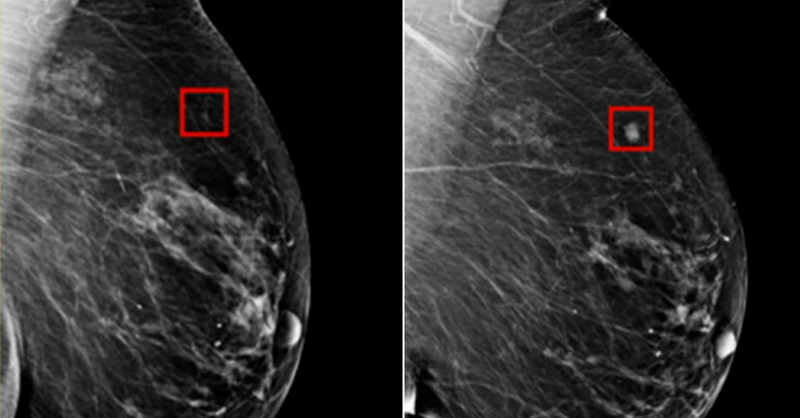

A new type of Artificial Intelligence can detect breast can.cer 5 years before diagnosis

Researchers have introduced a new, interpretable model designed to predict five-year breast cancer risk from mammograms, according to a study recently published in Radiology. Breakthroughs in AI...